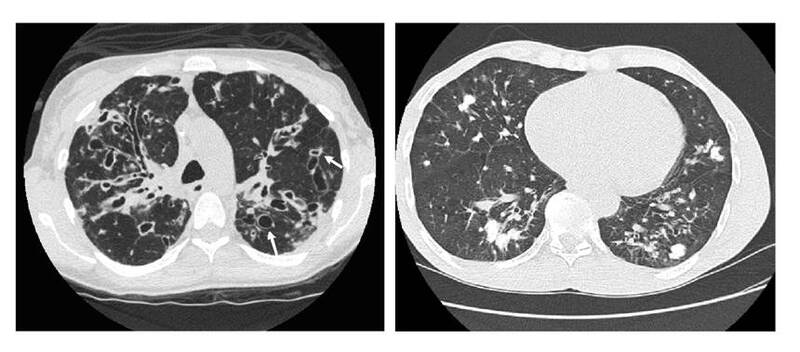

Luego del diagnóstico probable de paracoccidioidomicosis se continuó con la valoración clínica del paciente durante nueve meses, quien asistió al seguimiento con una nueva placa violácea dolorosa en la hélice izquierda (figura 4), aumento de la extensión de la lesión de la mucosa oral y persistencia de la lesión de la ceja izquierda. Además, se encontraron adenopatías cervicales e inguinales y se auscultó hipoventilación en las bases pulmonares con crepitación en la base pulmonar izquierda y sibilandas de predominio superior. En el reporte de latomografía se describieron múltiples granulomas calcificados, distribuidos en todos los segmentos y los lóbulos pulmonares, con predominio en las bases y la región parahiliar, asociados a cambios fibrocicatriciales. También se observaron algunos granulomas calcificados en los lóbulos superiores. Al valorar las lesiones más calcificadas en los lóbulos inferiores, se observó que algunas de ellas contenían material no calcificado en los bronquios dilatados, lo que sugirió la posibilidad de bronquiectasias (figuras 5A y 5B). Se repitió la toma de muestras para estudio con raspado exhaustivo de las lesiones de la mucosa oral, la ceja y la hélice izquierda, y se hizo venopunción para la obtención de suero.